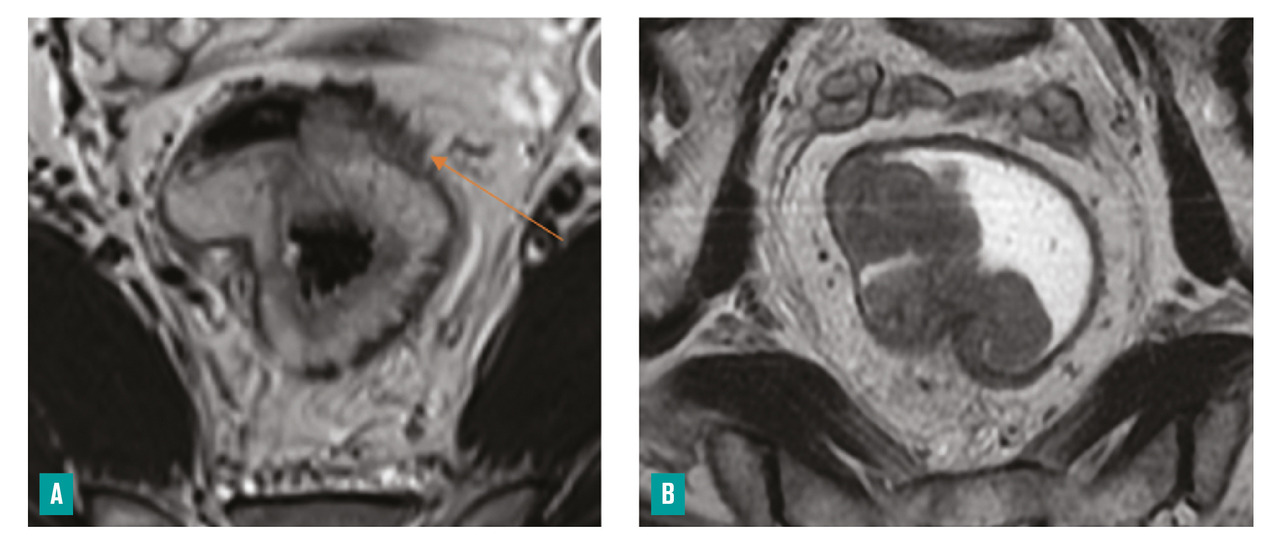

– la distance entre le pôle inférieur de la tumeur et la marge anale et/ou le bord supérieur du sphincter interne (fig. 3 ) ;

– la présence ou non d’arguments en faveur d’une histologie mucineuse, de plus mauvais pronostic (tumeur en hypersignal T2)4 [fig. 4 ] ;

– la marge circonférentielle (CRM) : distance la plus courte en millimètres entre le bord externe de la tumeur ou d’une adénopathie, d’un nodule tumoral, d’un embole vasculaire extramural et le fascia recti, ainsi que sa localisation horaire (fig. 3 ) ;

– la distance entre le pôle inférieur de la tumeur et la marge anale et/ou le bord supérieur du sphincter interne (

– la présence ou non d’arguments en faveur d’une histologie mucineuse, de plus mauvais pronostic (tumeur en hypersignal T2)4 [

– la marge circonférentielle (CRM) : distance la plus courte en millimètres entre le bord externe de la tumeur ou d’une adénopathie, d’un nodule tumoral, d’un embole vasculaire extramural et le fascia recti, ainsi que sa localisation horaire (